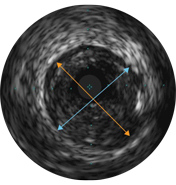

Диаметры сосудов можно определять в проксимальных и дистальных контрольных точках за счет значений диаметров просветов, средних диаметров стенок (в центральной точке между просветом и сосудом) или диаметров сосудов.

ВСУЗИ помогает более точно определить степень и тип стеноза (т.е. минимальную площадь просвета (MLA), объем бляшки и кальций). Несмотря на то что ВСУЗИ позволяет выявить разрыв бляшки, наличие тромбов и диссекции, кальций наиболее распространен при рутинных ЧКВ. Оказывая большее влияние на стратегию стентирования, кальций отображается в виде очень ярких участков с акустическим затенением, которое блокирует изображение сзади. Также могут наблюдаться реверберации.